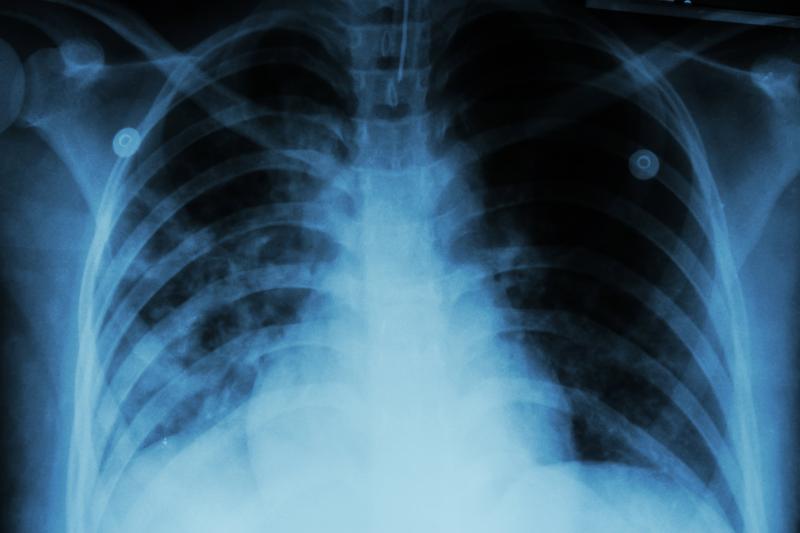

Factors associated with unsuccessful study outcomes included increasing age (>64 years vs 35–44 years: adjusted hazard ratio [aHR], 2.61), HIV-positive status (aHR, 1.53), presence of bilateral pulmonary cavities on x-ray (aHR, 1.68), smoking history (aHR, 1.34), baseline anaemia (aHR, 1.46), unemployment (aHR, 1.37), elevated baseline liver enzymes (aHR, 1.40), and excessive alcohol use (aHR, 1.47).